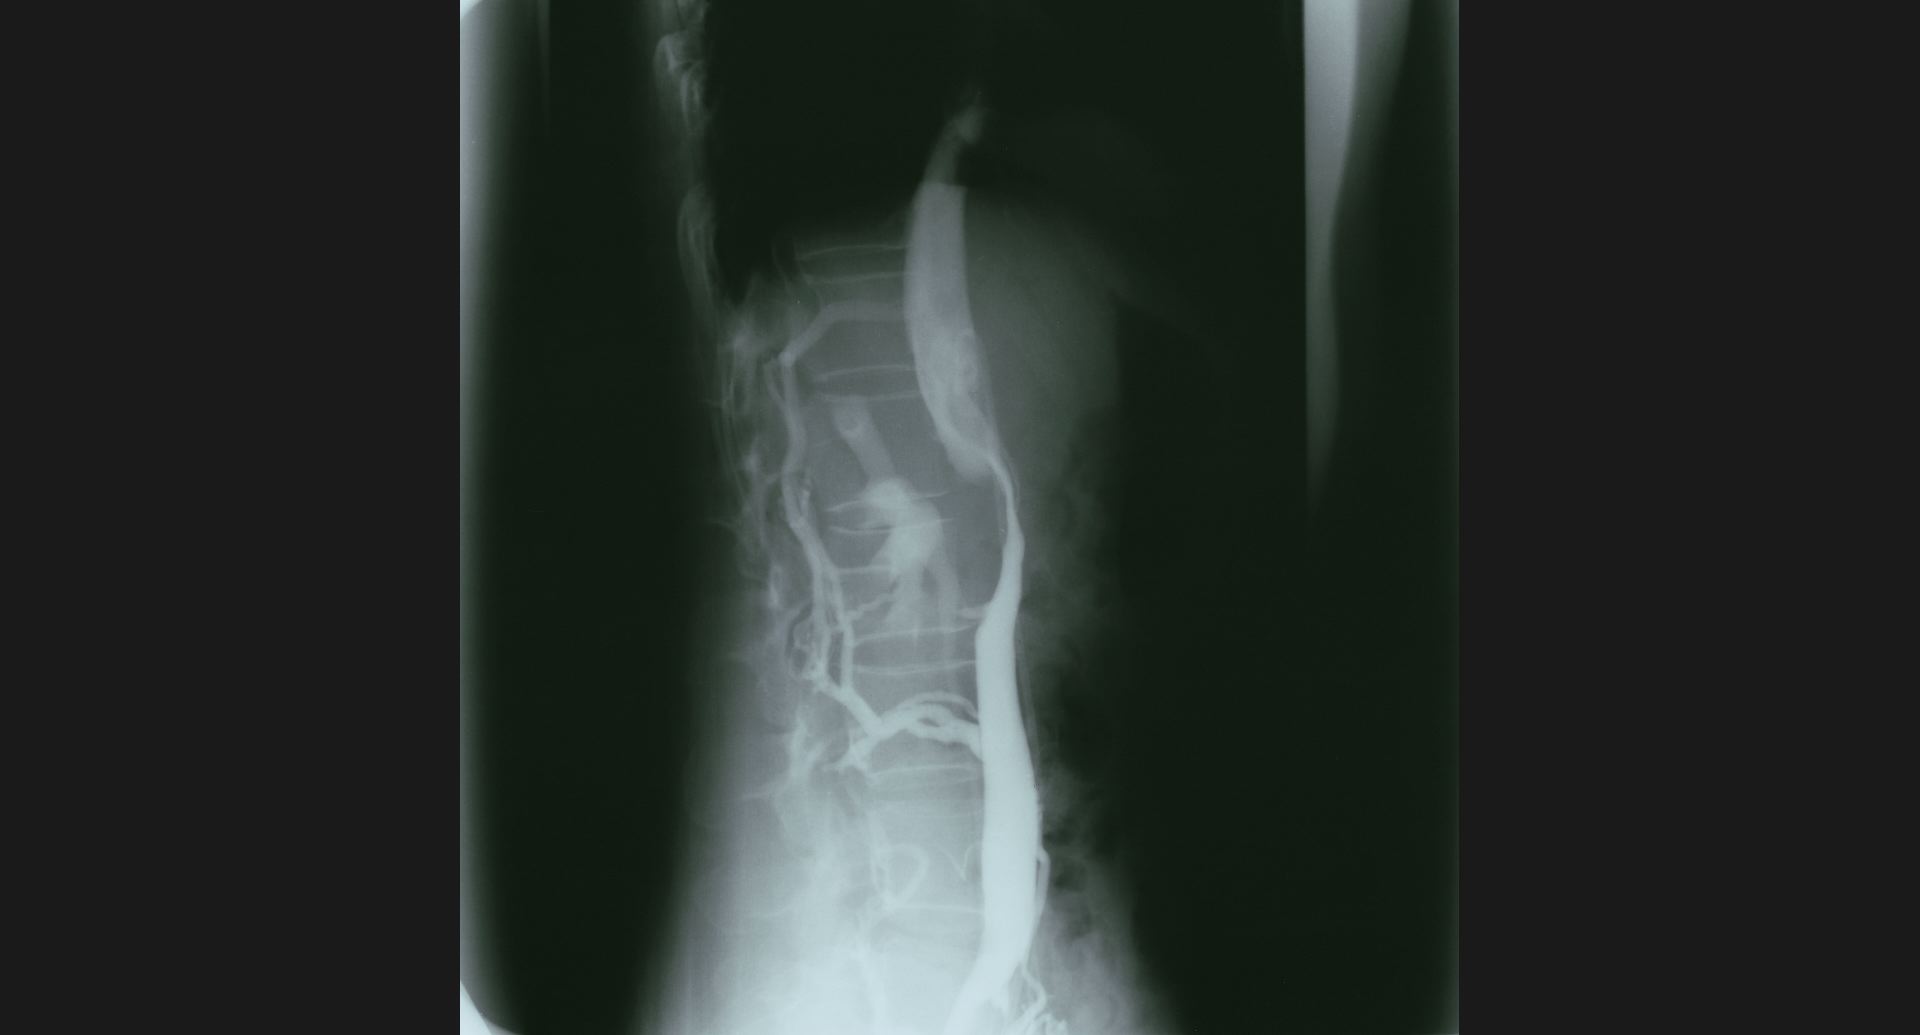

fig.10(99KB)

:SMA thrombosis (angiography)閉塞部位。腸管壁の細かい動脈。